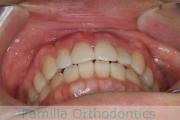

No.23V-385

- 主な症状:

- 叢生

- 年齢:

- 17歳

- 性別:

- 女性

- 抜歯部位

- 上:

- 44

- 下:

- 8448

- 主な使用装置:

- FEA 022

- 治療にかかった費用:

- 90万円

前歯のゆがみ、ズレがあるのを治したいということで来院されました。上下左右から小臼歯を抜歯して、マルチブラケット法にて治療をしました。1年8か月、20回程度の通院をしていただきました。叢生(でこぼこ、凹凸、ガタガタ)が強いため、保定をしっかりしないと後戻りのリスクがやや高いケースといえます。

- ≫治療前

-

上顎

下顎

前歯の関係など

右側

正面

左側

- ≫治療後